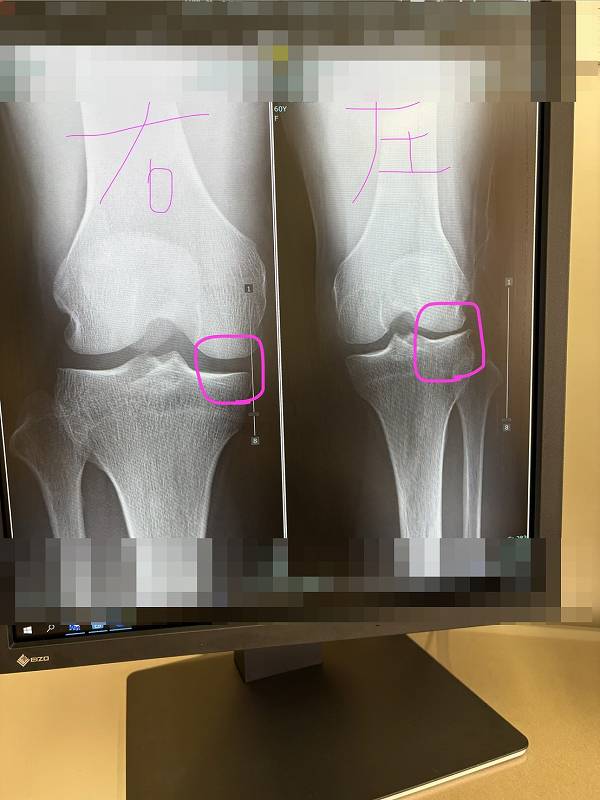

そのため、

スネの骨が外に回った状態のまま

レントゲンを撮れば、

膝の外側の関節の隙間は狭く写ります。

反対に、

スネが内側に回った状態で撮影すれば、

内側の関節の隙間が狭く写ります。

つまり、

レントゲンに写る「隙間」は、

関節の向きによっても変わるということです。